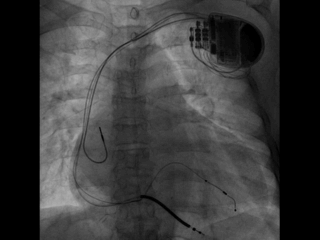

尝试抓捕器在右房抓捕runthough导丝成功,并进行牵拉

非常幸运,通过抓捕器的牵引力,电极顺利通过狭窄处,确定电极固定牢靠,抓捕器释放导丝并撤出,初步测试左室阈值满意,没有PNS。

依次植入右室除颤导线(6935M-DF4)和右房导线(4574),均测试满意,分别固定。

关键一步,鞘中鞘和递送鞘管的切除,均比较顺利,电极无移位。

AP

LAO45

RAO30

固定左室电极,连接CRTD(DTBC2QQ),手术最终影像